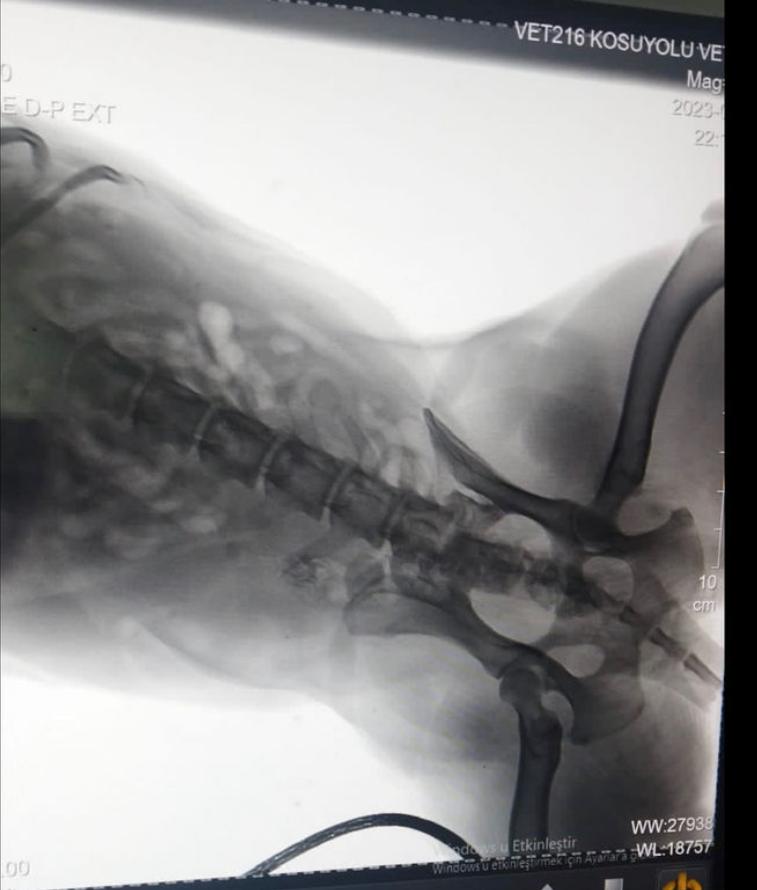

Silah ve köpeğin çıkardığı sesler üzerine dışarı koşan mahalle sakinleri, yaralı köpeği yakalayarak veteriner kliniğine götürdü. Kurşunun köpeğin omuriliğine isabet ettiği belirlendi. Köpeğin sağlık durumunun ciddiyetini koruduğu öğrenilirken, mahalle sakinleri polise giderek şikayetçi oldu.

Mahalle sakini Ela Durmazer ise, “Bu olay gerçekten çok üzücü. Bunun gibi birçok vaka var. Hayvan çok kötüydü. Omuriliğine saplanmış bir kurşun var. Şu an hayvan ameliyata da alınamıyor çünkü çok riskli bir ameliyat. Vücudunun güçlendirilmesi için mücadele ediyoruz. Bizim amacımız böyle şeylerin yapılmaması. Hiçbir koşulda hiçbir canlıya silahla ateş edilmemesi gerektiğini artık lütfen herkes duysun. Hiçbir canlıya bu yapılmayacak. Ve yapılmaması için tutanağı ben tutturdum. En azından hukuki sürecin başında olacağız” diye konuştu.

Kurşun köpeğin omuriliğine isabet etti